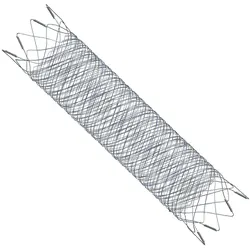

LVIS™ EVO™

Coil Assist Stents